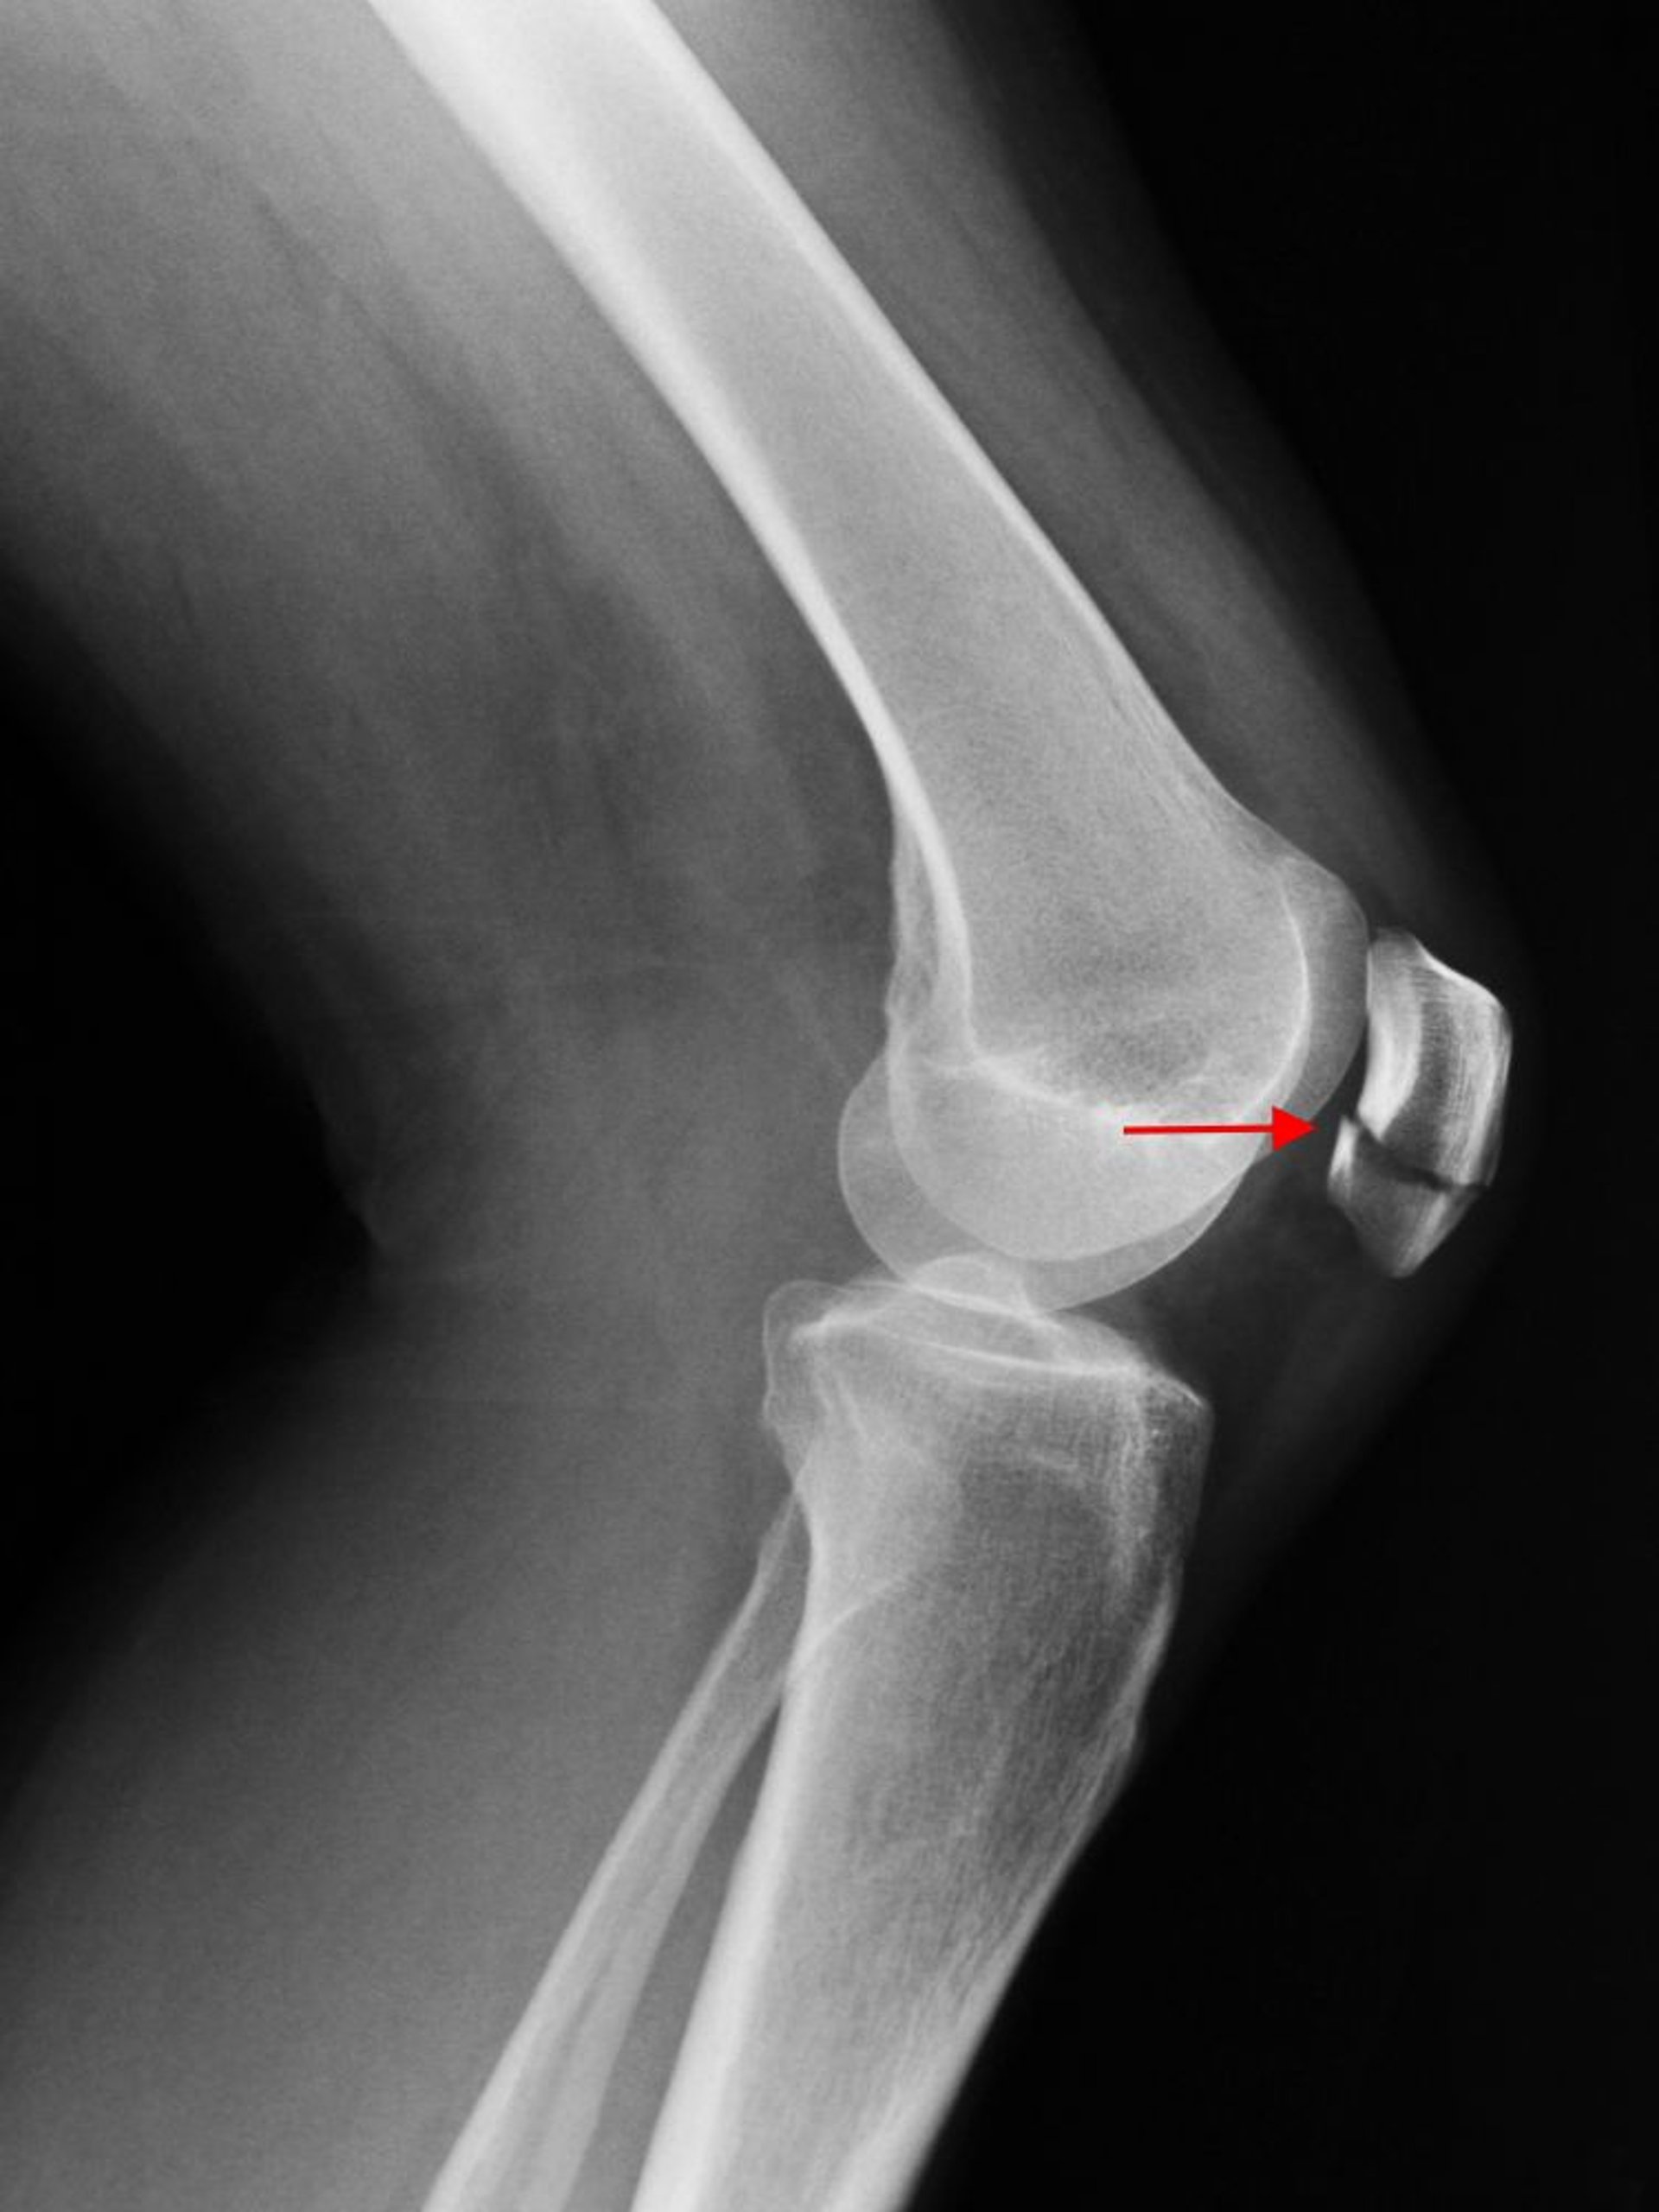

Une radiographie de profil du genou montre une fracture transversale de la rotule (flèche).

SCOTT CAMAZINE/SCIENCE PHOTO LIBRARY